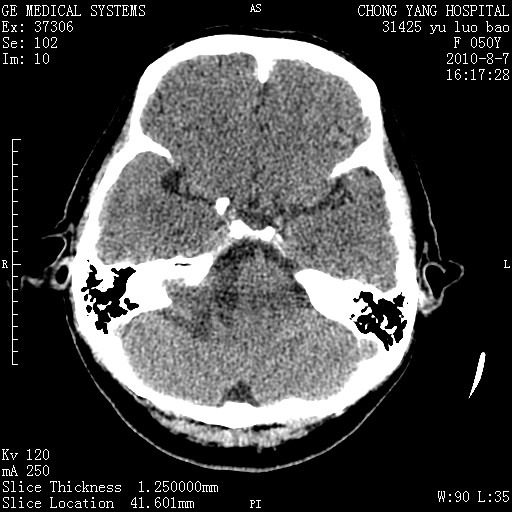

标题: CT28285:听力下降一年,头昏。 [打印本页]

标题: CT28285:听力下降一年,头昏。

右侧桥小脑角去等密度占位,右侧内听道扩大、骨质吸收,考虑:右侧听神经瘤,建议增强检查。

右侧内听道扩大、骨质吸收,中脑受压左移,考虑:右侧听神经瘤,建议增强检查。支持!

右侧桥小脑角区等密度占位,内耳道扩大,听神经瘤